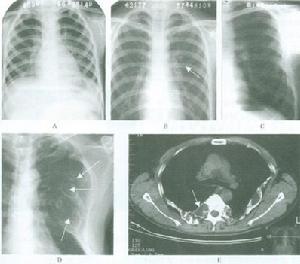

放射學檢查:繼發性甲狀旁腺功能亢進的放射學改變包括骨內膜、骨皮質和骨膜下的骨吸收,終端指、趾骨的腐蝕,囊腫形成,骨膜的neostosis和骨硬化,其中骨膜下骨吸收是最常見的放射學改變,主要見於指骨, 還可見於骨盆骨、鎖骨遠端以及肋骨、尺骨、脛骨和下頜骨下方的表層。骨硬化的放射學改變,為骨的密度增加,常見於椎體 骨盆、肋骨、鎖骨和各種長骨的乾骺端, 骨軟化的診斷有賴於骨活檢。放射學的惟一發現是Loosers帶的出現和假性骨折,骨密度常降低,但不足以診斷骨軟化。骨質減少是指放射學檢查發現的骨密度減低,常見於長期腎功能衰竭做血透治療者。骨軟化、繼發性甲狀旁腺功能亢進和骨質疏鬆經放射學檢查都可發現骨密度減低,很難單憑放射性特點來判斷骨質減少的原因。